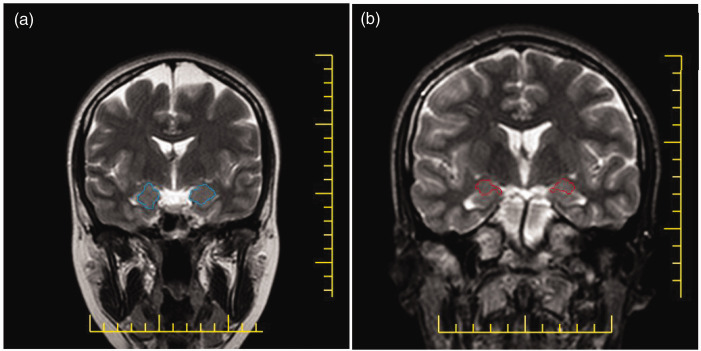

目的自杀的神经学原因仍然知之甚少。这项研究试图确定杏仁核体积和自杀行为之间是否存在关联。方法本研究纳入193例,其中健康对照108例,有自杀企图史者85例。对每个参与者进行矢状面磁共振成像,并使用徒手描摹独立确定左右杏仁核的横截面积。杏仁核的总体积是由切片的厚度乘以区域的总和来确定的。结果与对照组相比,有自杀未遂史的患者右侧和左侧杏仁核体积均显著减小(p = 0.018),左侧杏仁核体积显著减小(p = 0.036)。接收机工作特性分析确定了两个半球的截止值为1825 mm³。右侧杏仁核的灵敏度和特异性分别为30.6%和88%,左侧杏仁核的灵敏度和特异性分别为31.8%和84.3%。这是第一个表明自杀未遂者左右杏仁核体积显著减少的研究,接受者操作特征分析显示了良好的特异性(84.3%-88%)。根据这些发现,减少的杏仁核体积可能是识别那些有自杀倾向的人的一个有用的生物标志物。

ObjectiveThe neurological causes of suicide remain poorly understood. This study sought to ascertain whether there is a correlation between amygdala volume and suicidal behavior.MethodsThis case-control retrospective study included 193 participants-108 healthy controls and 85 individuals with a history of suicide attempts. Sagittal magnetic resonance imaging was conducted for each participant, and cross-sectional areas of the left and right amygdala were determined independently using freehand tracing. The total volume of the amygdala was determined by multiplying the thickness of the slices by the sum of the regions.ResultsPatients with a history of suicide attempts had significantly decreased amygdala volumes on both the right (p =0.018) and left (p =0.036) sides compared with controls. Receiver operating characteristic analysis determined a cutoff value of 1825 mm³ for both hemispheres. The cutoff sensitivity and specificity for the right amygdala were 30.6% and 88%, whereas the values for the left amygdala were 31.8% and 84.3%, respectively.ConclusionsThis is the first study to show that individuals who had attempted suicide had considerably decreased left and right amygdala volumes, with receiver operating characteristic analysis indicating good specificity (84.3%-88%). According to these findings, a reduced amygdala volume might be a useful biomarker for identifying those who are at risk of attempting suicide.